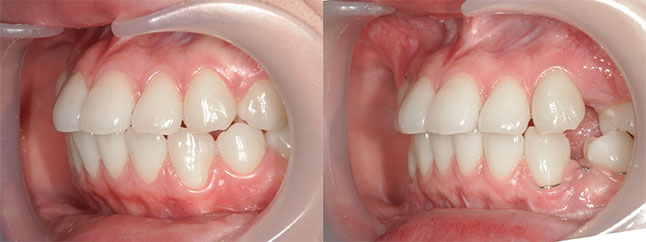

【治療内容】出っ歯、口元の膨らみが気になると当院を受診されました。上の前歯と歯茎が前方にポジショニングしており、下の前歯も歯茎から前に出ておりました。

<上下セットバック>

歯と歯茎を上は、5oバック、2oアップ、下は5oバックし固定しました。

※口ゴボ感が改善し、ご満足いただけました。

※afterは術後3か月時の写真です。

【費用】上下セットバック 2,307,800円(税込)

【リスク】感染・腫れ・出血・知覚鈍麻など